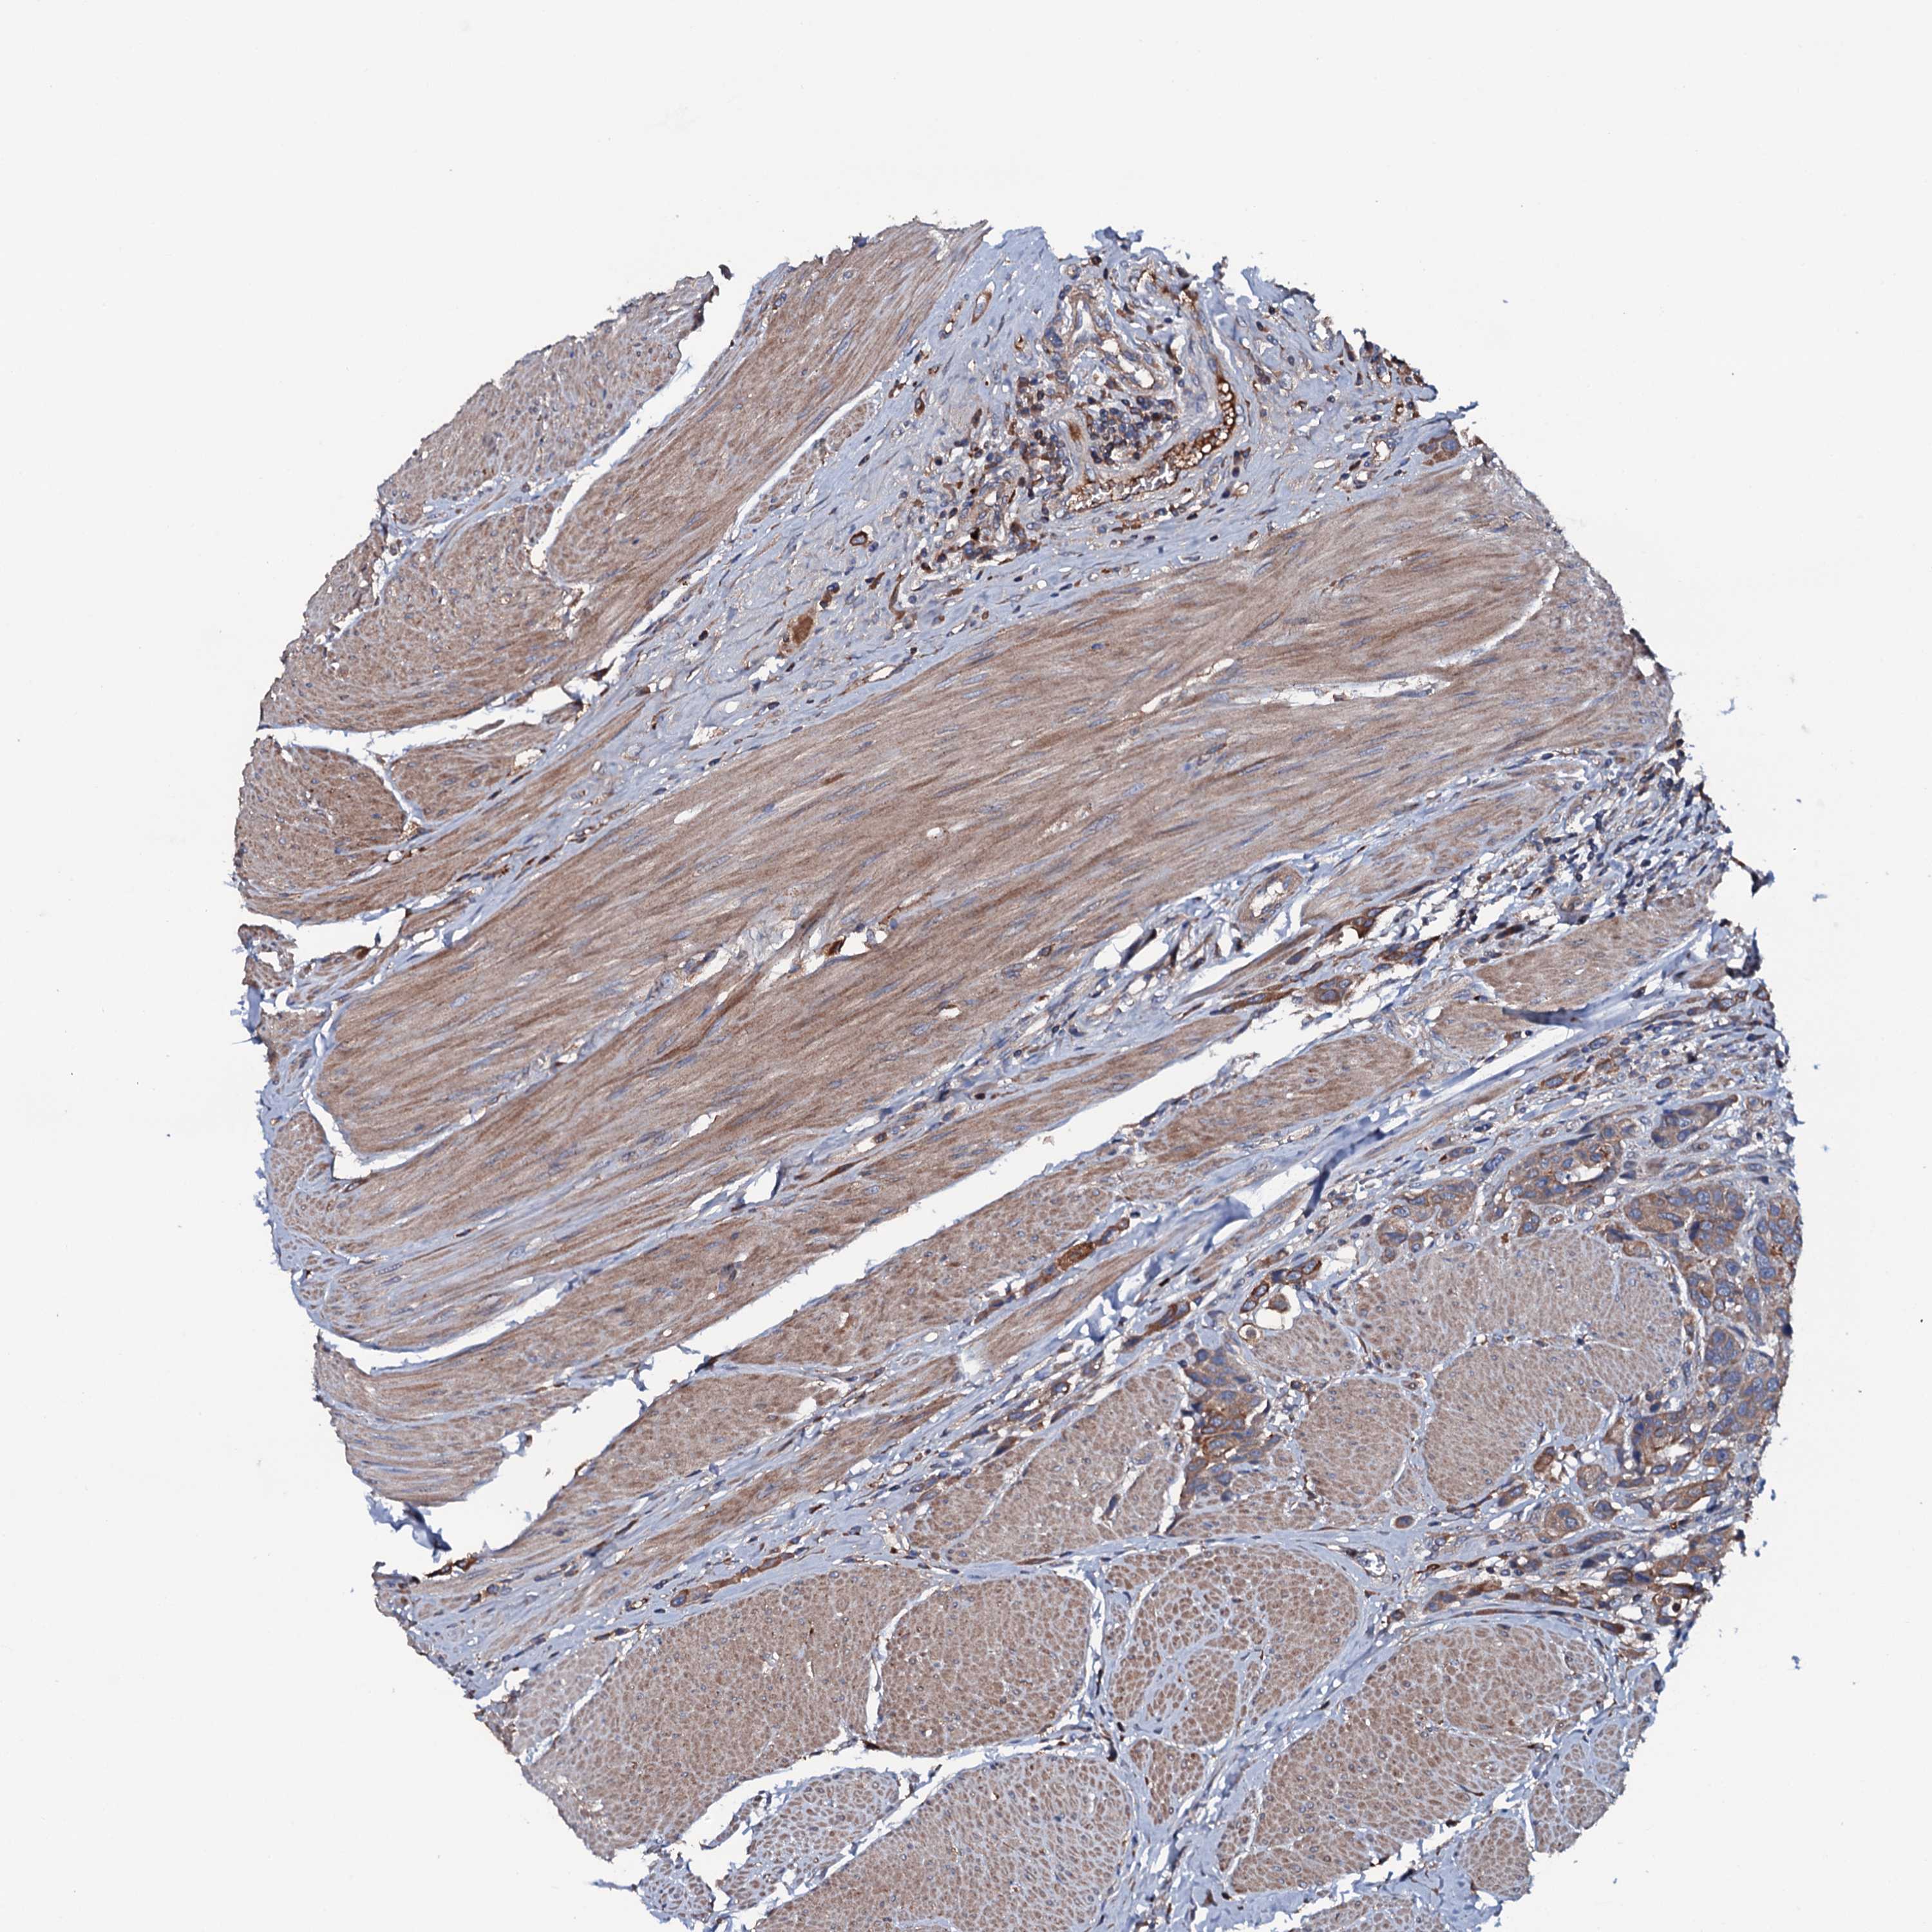

UROTHELIAL CANCER - Protein expressioni

A mouse-over function shows sample information and annotation data. Click on an image to view it in a full screen mode. Samples can be filtered based on level of antibody staining by selecting one or several of the following categories: high, medium, low and not detected. The assay and annotation is described here.

Note that samples used for immunohistochemistry by the Human Protein Atlas do not correspond to samples in the TCGA dataset.

Antibody stainingi

Antibody staining in the annotated cell types in the current human tissue is reported as not detected, low, medium, or high, based on conventional immunohistochemistry profiling in selected tissues. This score is based on the combination of the staining intensity and fraction of stained cells.

Each image is clickable and will lead to virtual microscopy that enables deeper exploration of all samples and also displays staining intensity scores, fraction scores and subcellular localization as well as patient and tissue information for each sample.

Antibody HPA020873

Antibody HPA040413

Staining

High

Medium

Low

Not detected

Intensity

Strong

Moderate

Weak

Negative

Quantity

>75%

75%-25%

<25%

None

Location

Nuclear

Cytoplasmic/membranous

Cytoplasmic/membranous,nuclear

Urothelial carcinoma, High grade

Urothelial carcinoma, Low grade

Urothelial carcinoma, NOS